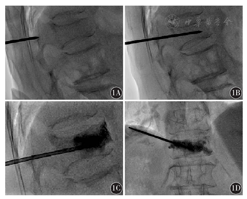

30例患者共36个椎体,其中腰椎12个,胸椎24个,均成功实施了骨水泥治疗,骨水泥的用量为2~6 ml。手术过程如图1所示。

1A:穿刺针体表定位;1B:穿刺针进入腰1椎体;1C:注入骨水泥矢状位成像;1D:注入骨水泥冠状位成像